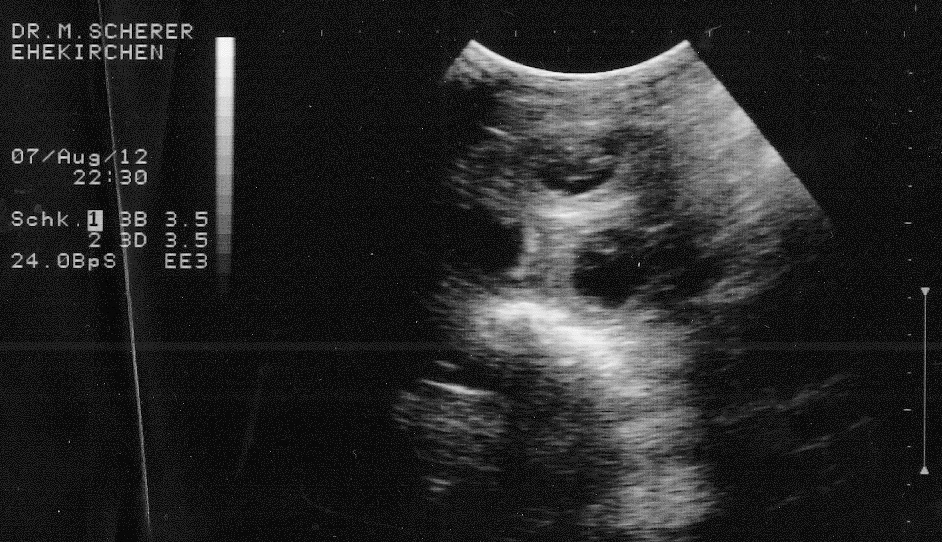

Ultraschallbild von 3 Wochen alten Embryonen